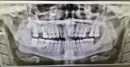

Две недели назад мне удалили зуб мудрости. Сейчас обнаружила на десне ближе к горлу, что торчит что то. Не болит если в покое, если нажать, есть неприятные ощущения. Предполагаю, что это точит кость из лунки. Зуб рос не ровно, упирался в 7-ку.

Прикрепленые фото

На снимке этого конечно диагностировать невозможно. Скорее мы имеем дело с экзостозом. Обратитесь к лечащему врачу.